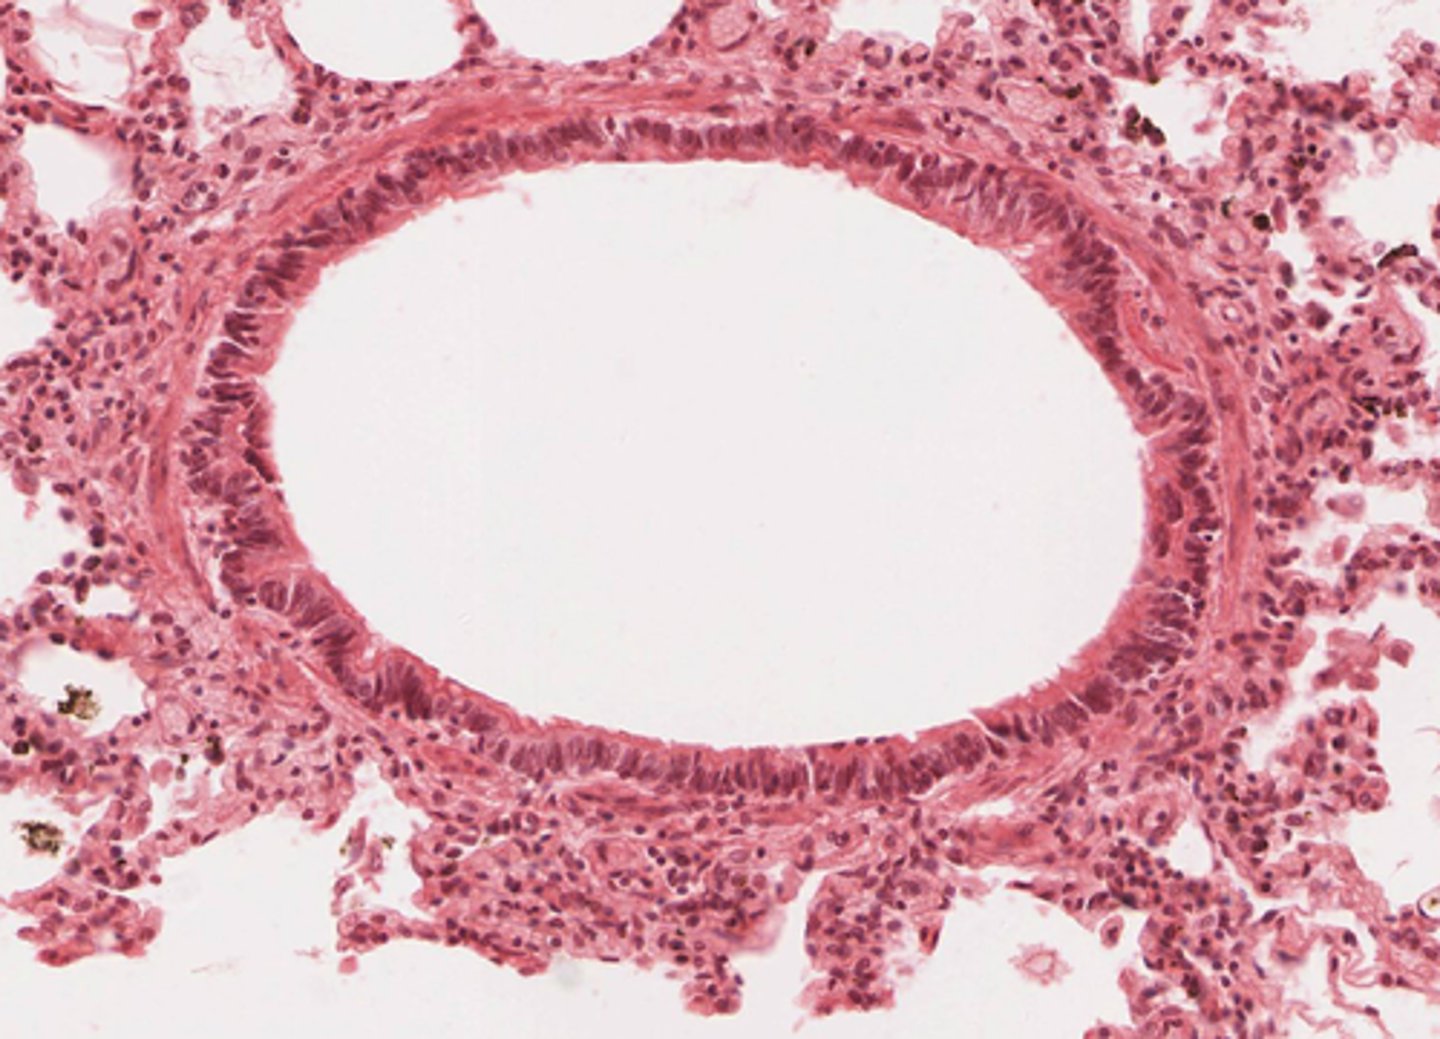

bronchioles

Identify the organ in the micrograph below.